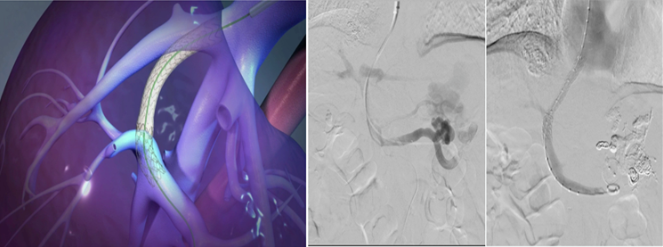

一“疏”:经颈静脉肝内门体分流术(TIPS)或 经肠系膜上静脉肝外门体分流术(TEPS),建立人工分流道从根本上解决门静脉高压,为患者搭建生命通道!

杜大哥的症状更适合TIPS,对于合并门静脉海绵样变和门静脉系统多发血栓的患者,可以采用TEPS技术。